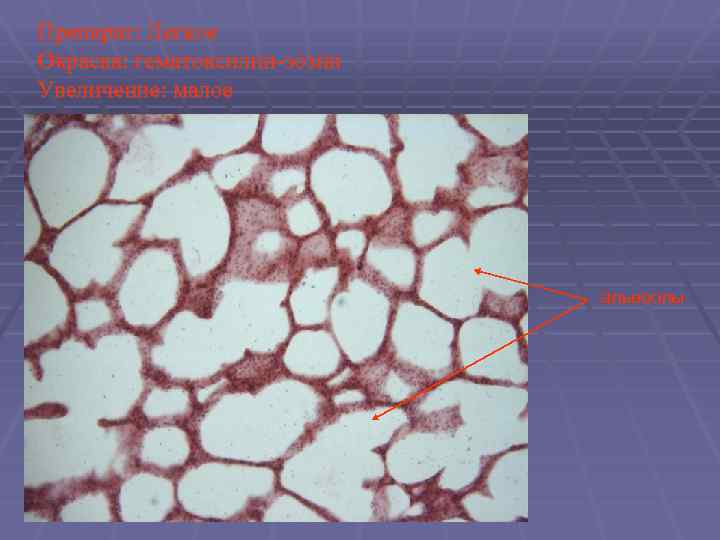

Препарат: Легкое Окраска: гематоксилин-эозин Увеличение: малое альвеолы